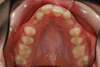

Intra Orale Supérieure